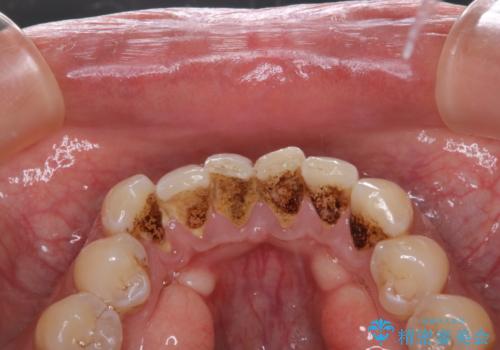

大好きなブラックコーヒーによる歯の着色を綺麗にしたい